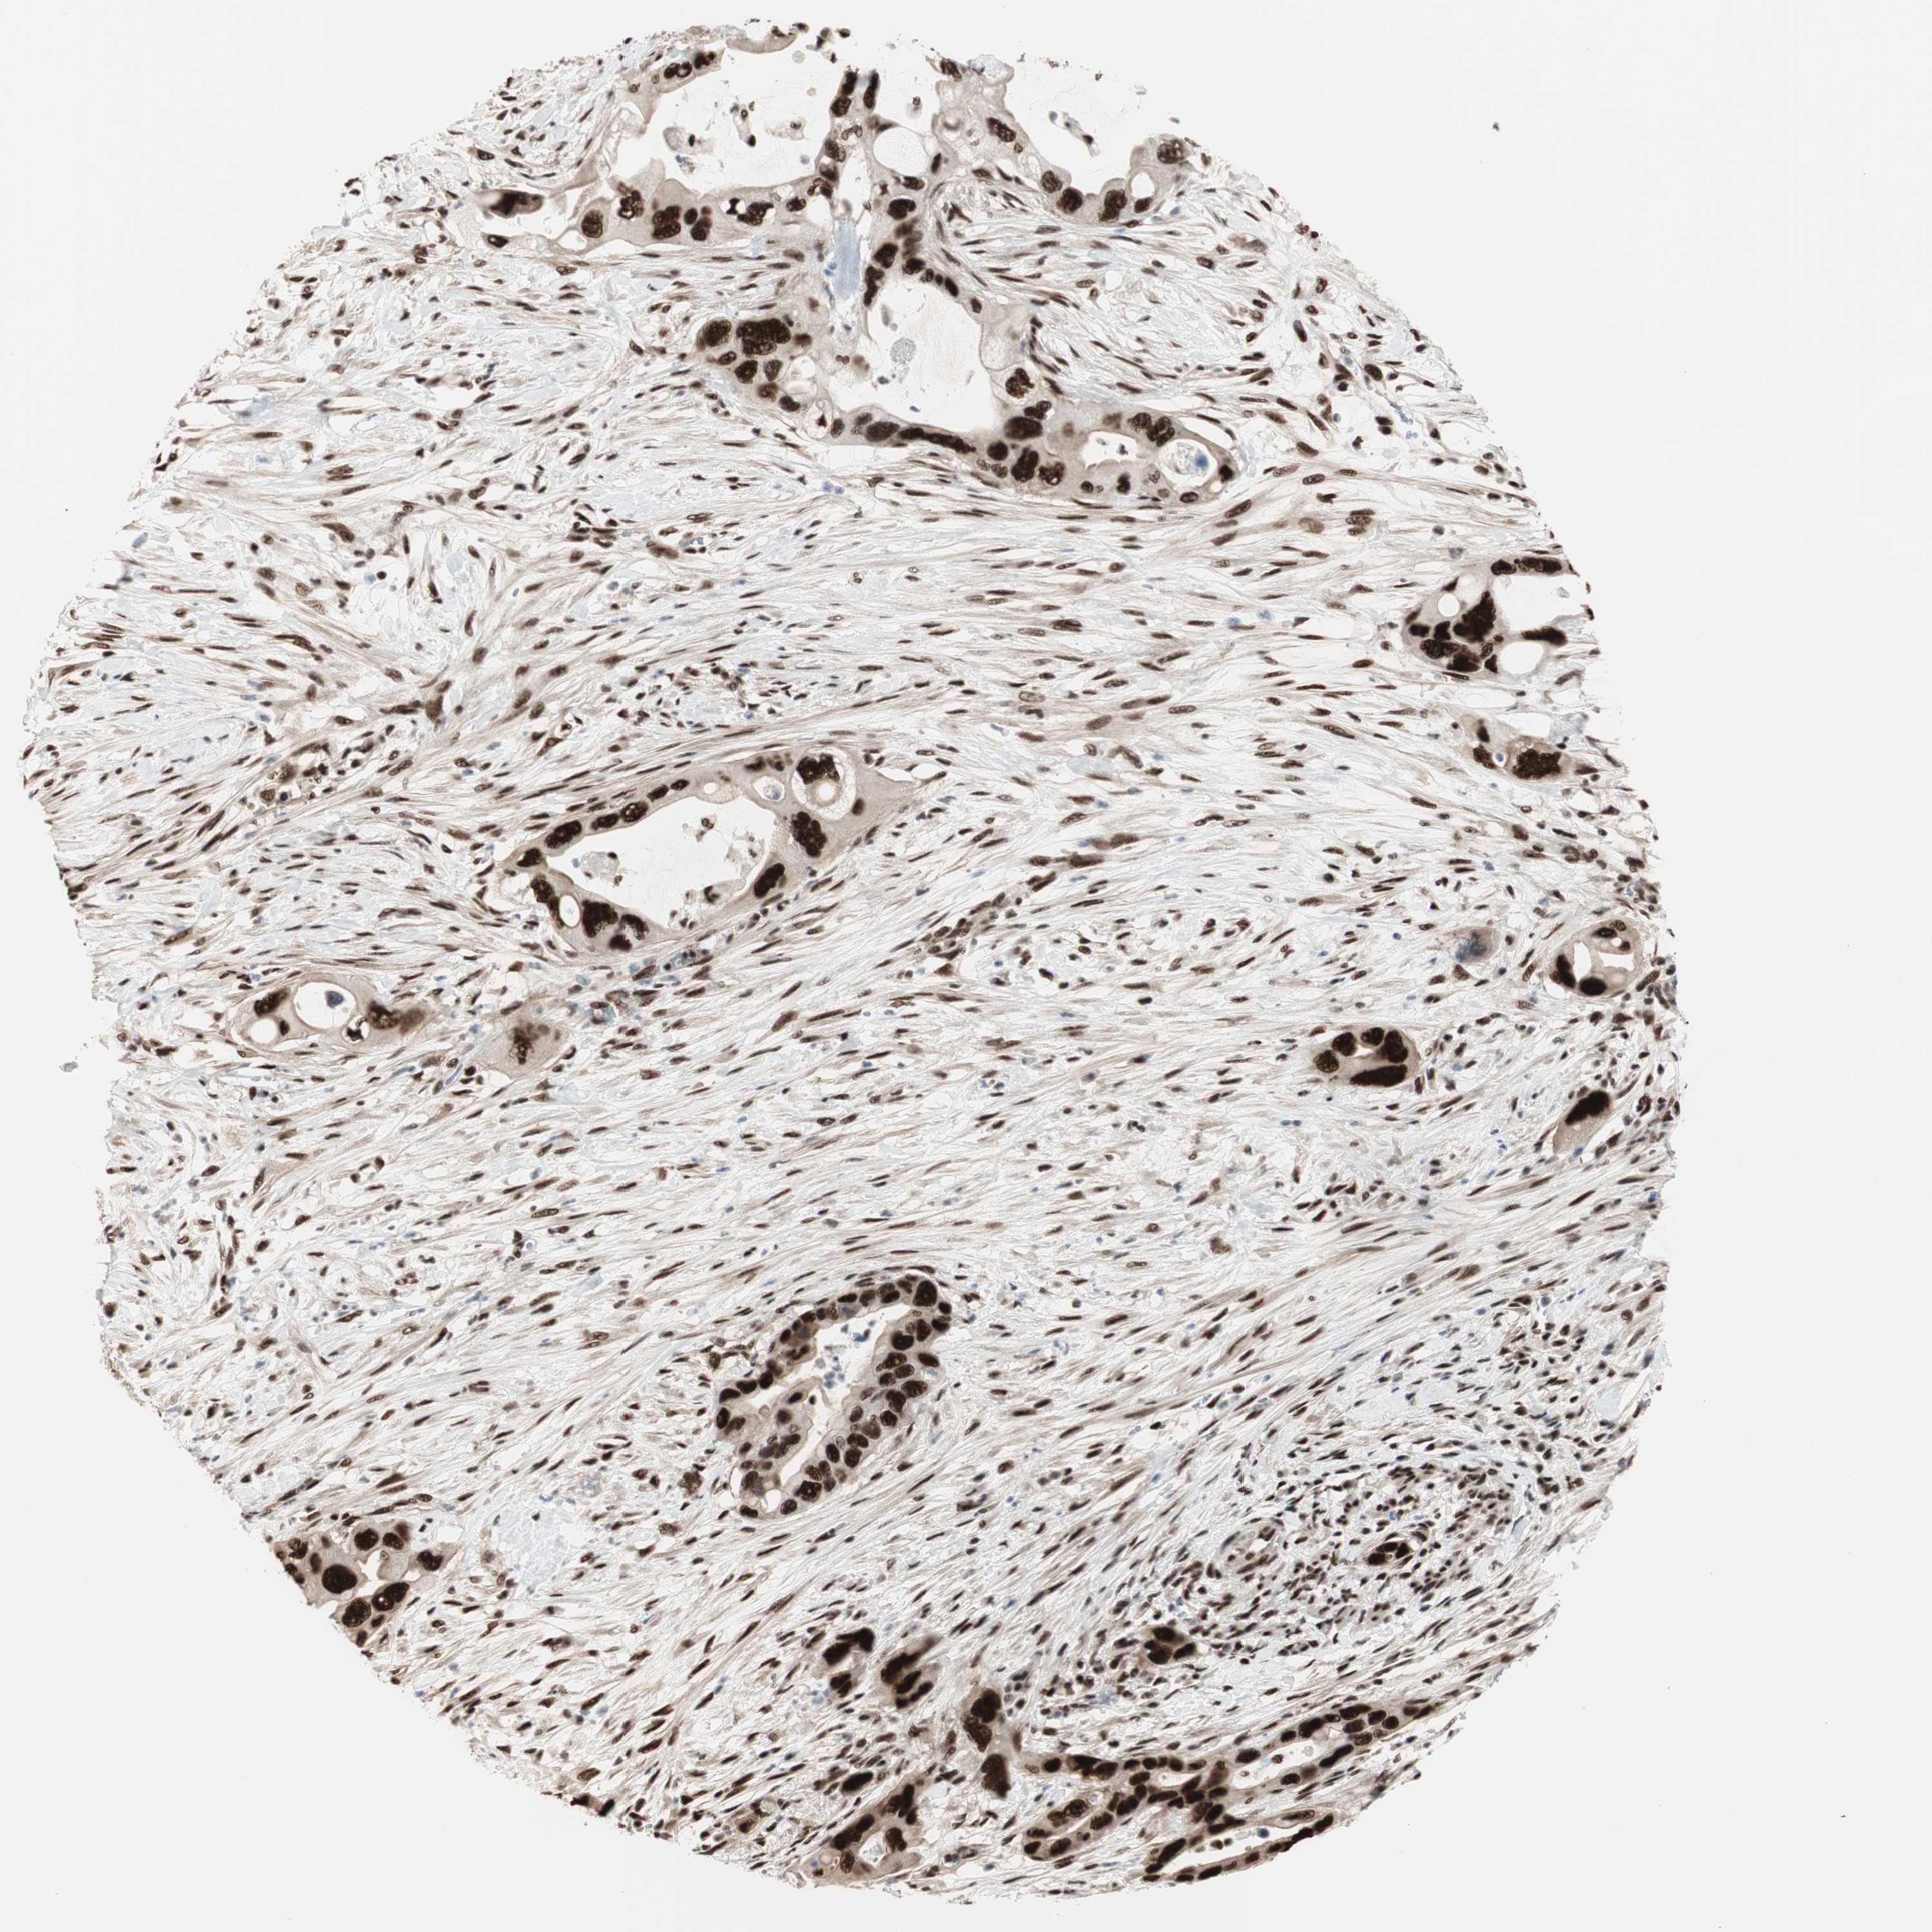

PANCREATIC CANCER - Protein expressioni

A mouse-over function shows sample information and annotation data. Click on an image to view it in a full screen mode. Samples can be filtered based on level of antibody staining by selecting one or several of the following categories: high, medium, low and not detected. The assay and annotation is described here.

Note that samples used for immunohistochemistry by the Human Protein Atlas do not correspond to samples in the TCGA dataset.

Antibody stainingi

Antibody staining in the annotated cell types in the current human tissue is reported as not detected, low, medium, or high, based on conventional immunohistochemistry profiling in selected tissues. This score is based on the combination of the staining intensity and fraction of stained cells.

Each image is clickable and will lead to virtual microscopy that enables deeper exploration of all samples and also displays staining intensity scores, fraction scores and subcellular localization as well as patient and tissue information for each sample.

Antibody HPA008926

Adenocarcinoma, NOS